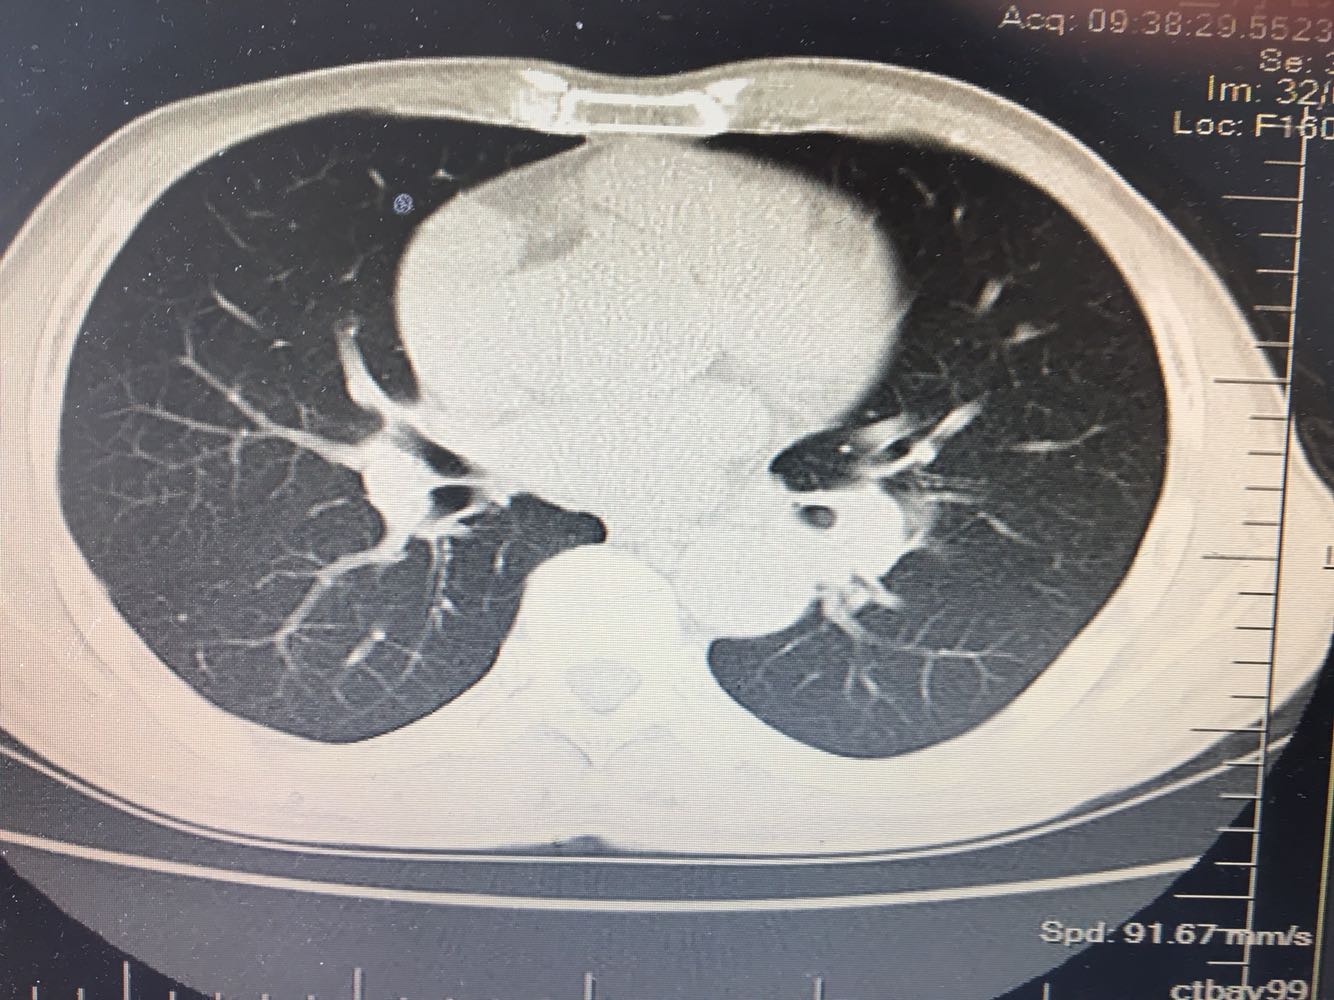

左肺下叶鳞癌

男,63岁,咳嗽1个月入院,患者自述1个月前无诱因咳嗽,阵发性干咳,无痰,时有血丝,无发热,左胸痛,活动后气短,静滴头孢13天无好转,门诊查肺CT后以 肺占位收入我科,病来饮食睡眠可,体重明显下降。既往疝气术后1年,吸烟史30年,每日1包。

左肺癌

左肺中央型肺癌,是否可以手术,还是化疗,放疗,靶向治疗?